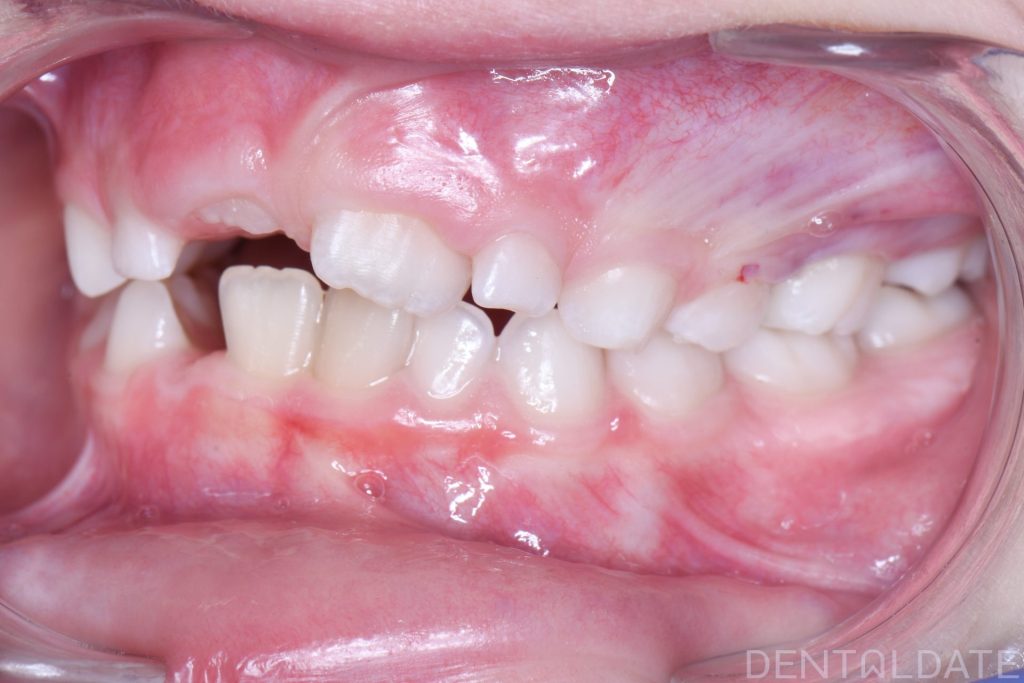

In this case, there was a severe lack of space for the permanent teeth, narrowing of the upper jaw, and the development of a malocclusion.